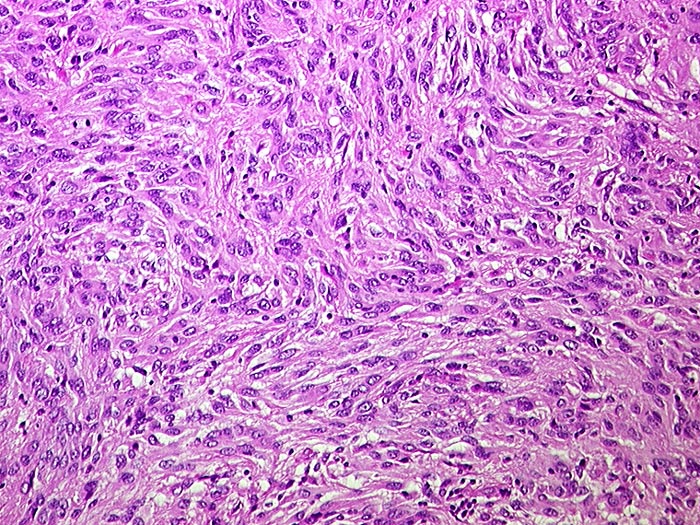

Makroskopisch imponieren kleine Tumoren als peritoneale, intramurale oder submuköse Knoten. Grössere Tumoren wölben sich oft vor und können ulzerieren. Die Schnittfläche ist weisslich und kann Einblutungen, Zysten, Fibroseareale oder Nekrosen aufweisen. Histologisch werden Spindelzelltyp (70%), Epitheloidzelltyp (20%) oder gemischtzelliger Typ (10%) unterschieden. Der histologische Subtyp scheint keinen Zusammenhang mit zugrundeliegender Mutation, Therapieansprechen und Prognose zu haben. Gelegentlich sind vor allem die kleineren Tumoren zellarm und kollagenreich.

• Der Tumor besteht aus längs und quer getroffenen Faszikeln spindelförmiger Tumorzellen, welche an glatte Muskelzellen oder Schwannzellen erinnern.